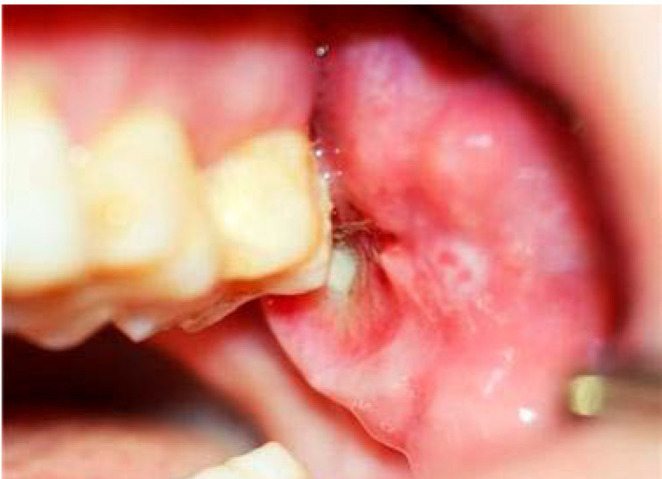

Basal cell adenocarcinoma, considered to be the malignant counterpart of basal cell adenoma, is a rare, low-grade malignant tumor of the salivary glands, accounting for 1-2% of salivary gland malignancies. It predominantly affects the parotid gland, while involvement of the minor salivary glands is exceptionally rare. This report presented a case of basal cell adenocarcinoma involving the left retromolar trigone in a 54-year-old woman. The initial provisional diagnosis suggested a benign or low-grade malignant salivary tumor. Advanced magnetic resonance imaging techniques, including diffusion-weighted imaging and apparent diffusion coefficient analysis, aided in the preoperative prediction of malignancy, and an incisional biopsy confirmed the diagnosis of basal cell adenocarcinoma. This case underscored the challenge of distinguishing basal cell adenocarcinoma from benign salivary tumors, as clinical and imaging features often overlap. Surgical excision remains the primary treatment, yielding favorable outcomes; however, long-term follow-up is crucial due to the risk of recurrence.

Abstract Image